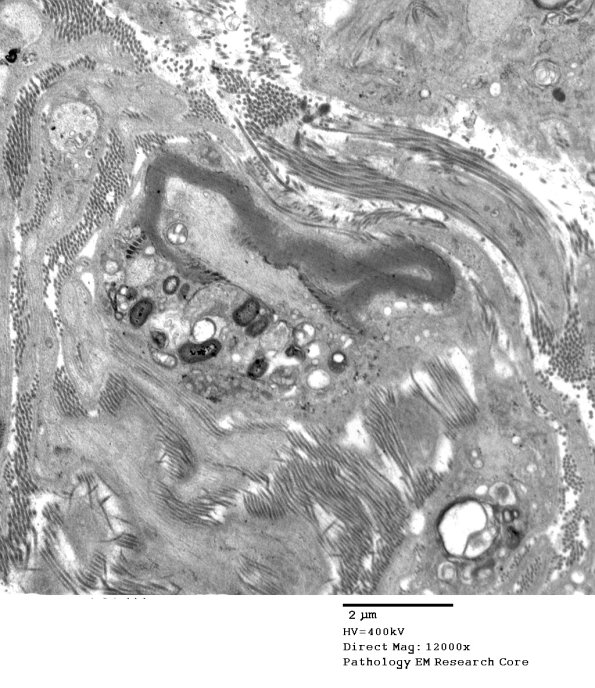

2D4,5 A macrophage with myelin debris is intimately associated with a paranodal axon. (electron micrograph)